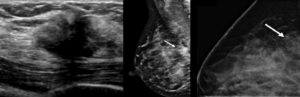

Кроме того, для диагностики молочной железы используются такие методы:

Маммография рак молочной железы

Женщинам надо помнить, что после достижения сорокалетнего возраста всем женщинам необходимо регулярно проходить маммографию. Компьютерная и магнито-резонансная томография дают наиболее точные диагностические результаты.

Микрокальцинаты нередко комбинируются с раками грудной железы в 42% и легко выявляются при рентгеновской маммографии. Рентгеновская маммография имеет хорошие прогностические возможности в определении распространенности внутрипротоковых опухолей.

Рентгеновская дуктография ведущий метод диагностики внутрипротокового рака грудной железы, благодаря выявлению микрокальцинатов, которые являются подозрительными на злокачественность опухолевого процесса. Косвенными признаками непальпируемых раков являются микрокальцинаты, которые лучше выявляются при рентгеновской маммографии.

Поскольку микрокальцинаты являются одним из патогномоничных признаков злокачественности опухолевого процесса их обнаружение имеет существенную роль.